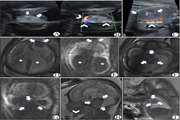

Congenital Disseminated Pyogenic Granuloma: A Case With Numerous Mucocutaneous and Visceral Lesions 1404/04/17 - 12:25